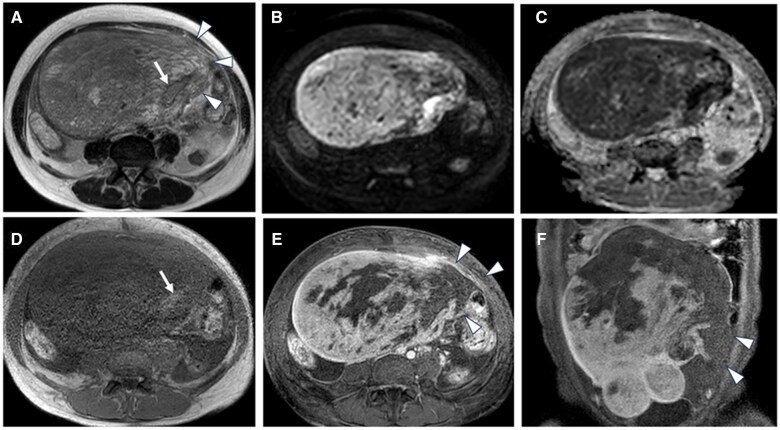

This case report describes a 47-year-old premenopausal woman who presented with abdominal discomfort and had been previously monitored for a suspected uterine leiomyoma. MRI revealed a 15 cm mass within the uterine body and slight intratumoural haemorrhage. One month later, the patient presented with acute abdominal pain and was admitted to the hospital. Contrast-enhanced CT and MRI scans showed significant tumour enlargement to 20 cm, with disruption along the left margin, haemorrhagic ascites, and potential dissemination to the omentum. Total hysterectomy, bilateral salpingo-oophorectomy, and retroperitoneal lymph node dissection revealed uterine leiomyosarcoma with extensive necrosis and rupture. Pathological examination classified the tumour as stage IIB under the International Federation of Gynecology and Obstetrics system, with confirmed omental metastasis. Despite adjuvant chemotherapy, the patient experienced pelvic recurrence 10 months later and died 15 months postoperatively. This case emphasizes the importance of prompt gynaecological intervention for uterine masses exceeding 10 cm, as the risk of rupture increases, particularly when malignancy cannot be excluded based on imaging. Rupture in such cases is associated with a higher risk of recurrence and poor prognosis, making early surgical resection a reasonable consideration. Radiologists should actively communicate these risks to gynaecologists to facilitate timely surgical decision-making and improve patient outcomes.